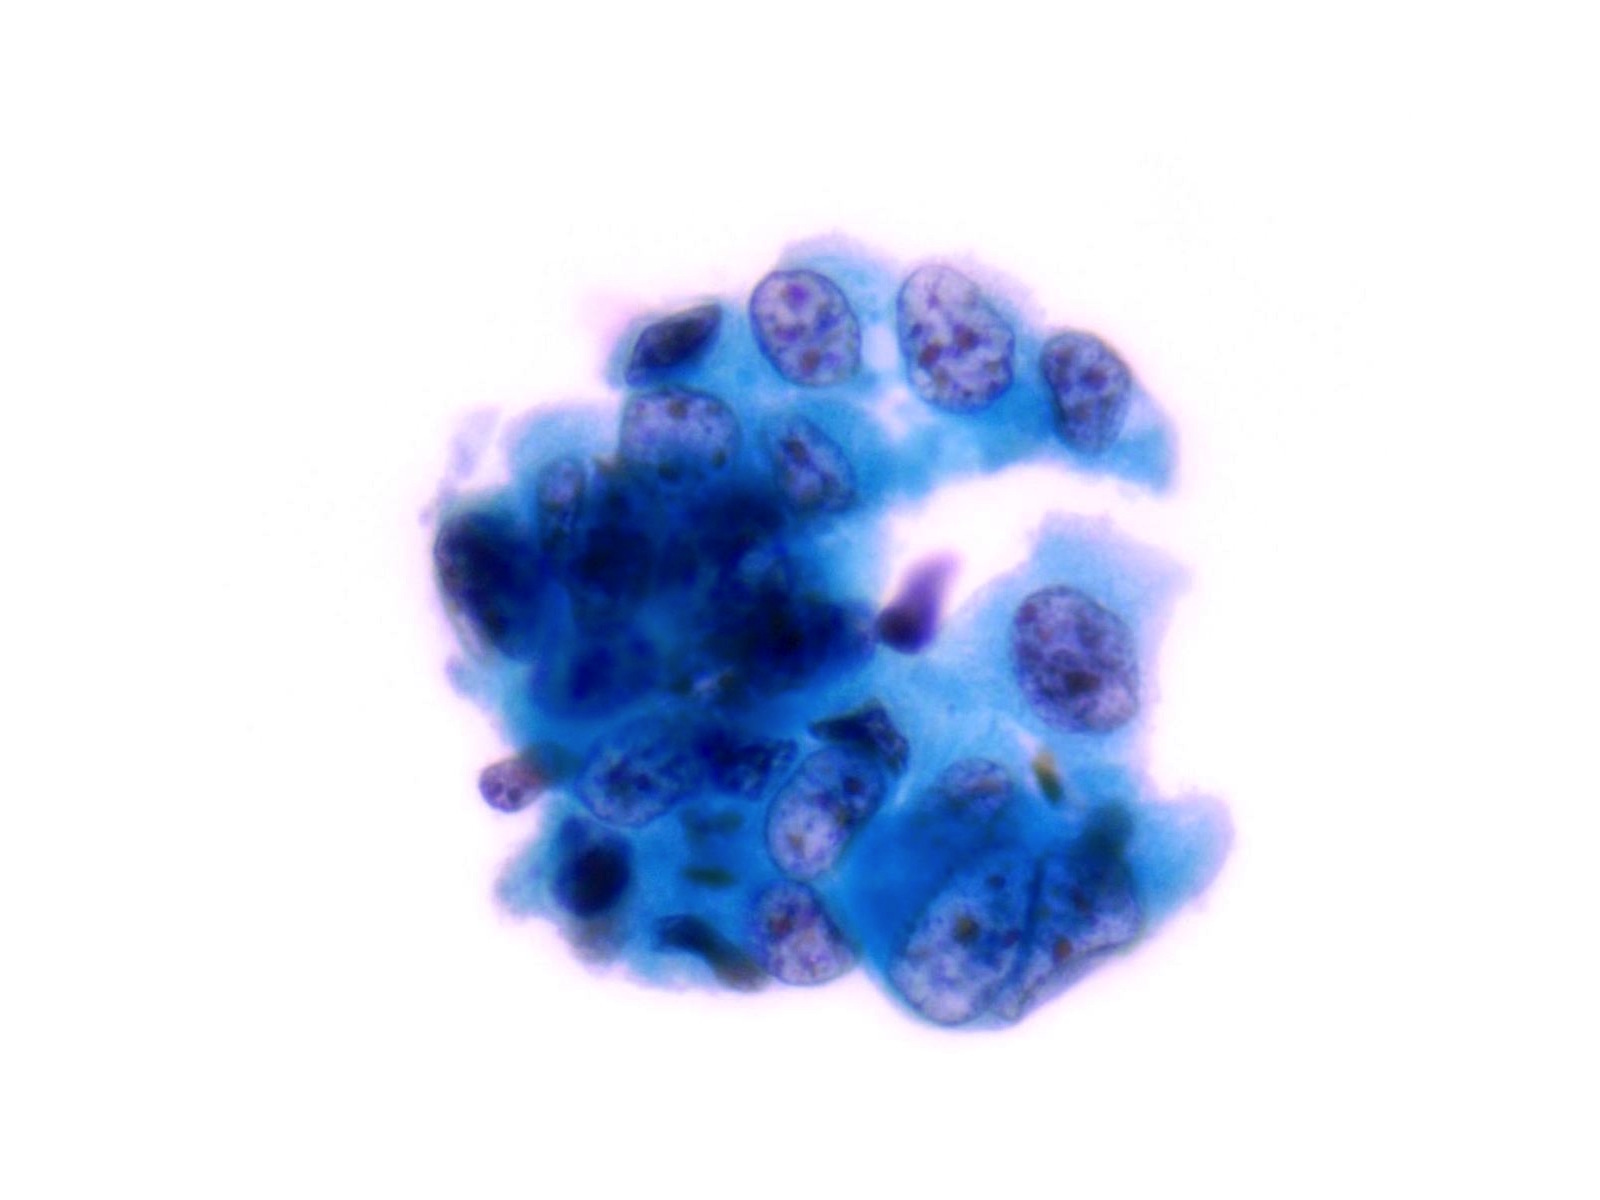

High Grade Urothelial Carcinoma (HGUC)

-

- HGUC is diagnosed on the basis of this criteria according to the Paris System consensus:

- Cellularity; at least 5 - 10 abnormal cells

- N:C ratio: 0.7 or greater

- Nucleus: moderate to severe hyperchromasia

- Nuclear membrane: markedly irregular

- Chromatin: coarse / clumped

- Other notable cytomorphologic features of HGUC are

- Cellular pleomorphism

- Marked variation in cellular size and shapes. i.e., oval, rounded, elongated or plasmacytoid (comet cells)

- Scant, pale or dense cytoplasm

- Prominent nucleoli

- Mitoses

- Necrotic debris

- Inflammation